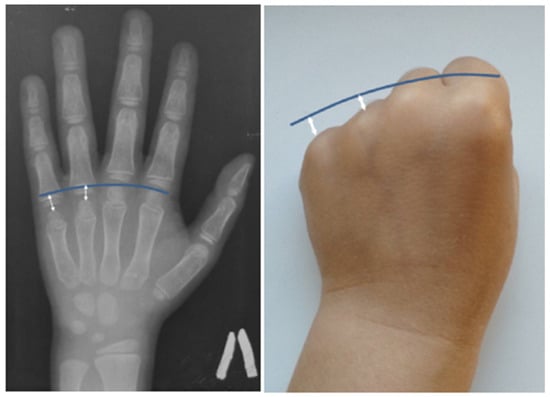

Multiple sclerotic lesions of the skull bones were found in the proband’s father, grandmother, and paternal uncle, confirmed by X-ray and CT examination of the skull. On the contrary, the physical examination of a cousin of a 7-year-old proband revealed only three elevated skull seals in the frontal and parietal–occipital regions, which were presented on the CT scan in the form of three rounded foci of osteosclerosis in the frontal and parietal bones with a thin sclerotic rim along the contour and with vacuum in the central sections in the shape of a doughnut. According to the results of a CT scan, by the age of 6 years, the proband did not have any sclerotic lesions of the skull.

Examination of an 11-year-old proband and his uncle of the same age revealed bony prominences of the calvaria in the forehead area 3 × 3 cm in size. In the mother and grandmother of the proband, the same formations were found in the forehead area 5 × 5 cm in size and at the back of the head 3 × 3 cm in size (Figure 4). Sclerotic lesions of the skull bones were found in all family members during X-ray and CT examination of the skull (Figure 5).

A lateral radiograph of the scull performed at the age of 30 years revealed sclerotic lesions involving the frontal, parietal, and temporal bones with the maximum size in the projection of the coronal suture. These findings were confirmed by a CT scan of the skull bones.

The skull lesions are a fascinating feature of the disease, limited to the vault of the skull. Standard skull X-rays reveal multiple areas of bone involvement, with the appearance of ring-shaped formations resembling a doughnut, lytic lesions of the skull vault, and thickening of the skull vault and/or base. In some cases, sclerotic lesions of the skull bones lead to the protrusion of the outer plate of the skull vault, clinically manifested as a palpable thickening in this area of the head (Figure 4). Skull lesions often progress asymptomatically and are usually detected incidentally on computed tomography (CT) or magnetic resonance imaging (MRI) of the brain. Characteristic skull bone lesions can be diagnosed with standard X-rays, but CT and MRI, by detecting small formations in the diploic space of the skull, allow for early diagnosis of the disease in patients with only multiple fractures in the absence of clinically palpable subcutaneous thickening of the head. It should be noted that doughnut-shaped skull lesions are not observed in early childhood due to age-related structural peculiarities (the diploic space is not well developed in children) and can only be detected at a later age [9]. With age, the number and size of lesion foci increase. In addition, it is important to verify these bone lesions as a benign process and differentiate them from other lytic lesions of the skull vault (intradiploic epidermoid cysts, hemangiomas, eosinophilic granulomas, etc.), including malignant primary and metastatic lesions [1,10,11]. The detection of typical changes in the skull vault bones in combination with the patient’s age, family history, and clinical symptoms of the disease is of fundamental importance for differential diagnosis with osteogenesis imperfecta and for establishing the correct diagnosis.

Figure 5. Lateral radiograph of the skull (F2 III-2): sclerotic lesions (white circles) and thickening (yellow arrows) of the bones. Axial CT scan of the skull vault (F2 I-2): doughnut-shaped lesions (yellow arrows) and significant thickening of the cranial bones (red arrows).